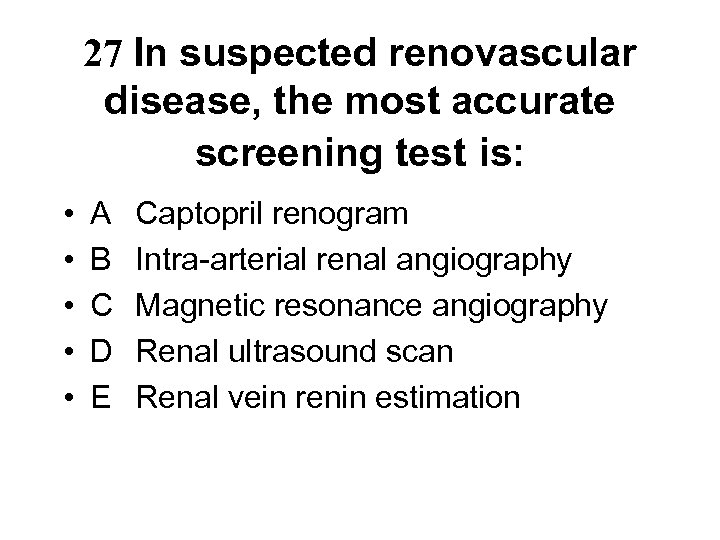

27 In suspected renovascular disease, the most accurate screening test is: • • • A B C D E Captopril renogram Intra-arterial renal angiography Magnetic resonance angiography Renal ultrasound scan Renal vein renin estimation

27 In suspected renovascular disease, the most accurate screening test is: • • • A B C D E Captopril renogram Intra-arterial renal angiography Magnetic resonance angiography Renal ultrasound scan Renal vein renin estimation

27. In suspected renovascular disease, the most accurate screening test is: • • • A B C D E Captopril renogram Intra-arterial renal angiography Magnetic resonance angiography Renal ultrasound scan Renal vein renin estimation

27. In suspected renovascular disease, the most accurate screening test is: • • • A B C D E Captopril renogram Intra-arterial renal angiography Magnetic resonance angiography Renal ultrasound scan Renal vein renin estimation

• • • Diagnosis - suspect in arteriopath with difficult HT or ACEI renal failure - renal sonar may show inequality of renal size (>1. 5 cms) - captopril renogram is ok screening test if renal function normal - MRA now considered best screening test - intra arterial renal angio is still the gold standard for diagnosis - renal vein renin ratio may predict response to revascularisation Treatment - control of HT avoiding ACEI/ARB if possible - aspirin and statin for their anti ischaemic effect - revascularisation by PTRA/stent if BRVD with >60% stenoses and pulmonary oedema, difficult HT or need to use ACEI/ARB • Outcome • - high mortality from extra renal vascular disease and don’t usually do well on dialysis

• • • Diagnosis - suspect in arteriopath with difficult HT or ACEI renal failure - renal sonar may show inequality of renal size (>1. 5 cms) - captopril renogram is ok screening test if renal function normal - MRA now considered best screening test - intra arterial renal angio is still the gold standard for diagnosis - renal vein renin ratio may predict response to revascularisation Treatment - control of HT avoiding ACEI/ARB if possible - aspirin and statin for their anti ischaemic effect - revascularisation by PTRA/stent if BRVD with >60% stenoses and pulmonary oedema, difficult HT or need to use ACEI/ARB • Outcome • - high mortality from extra renal vascular disease and don’t usually do well on dialysis